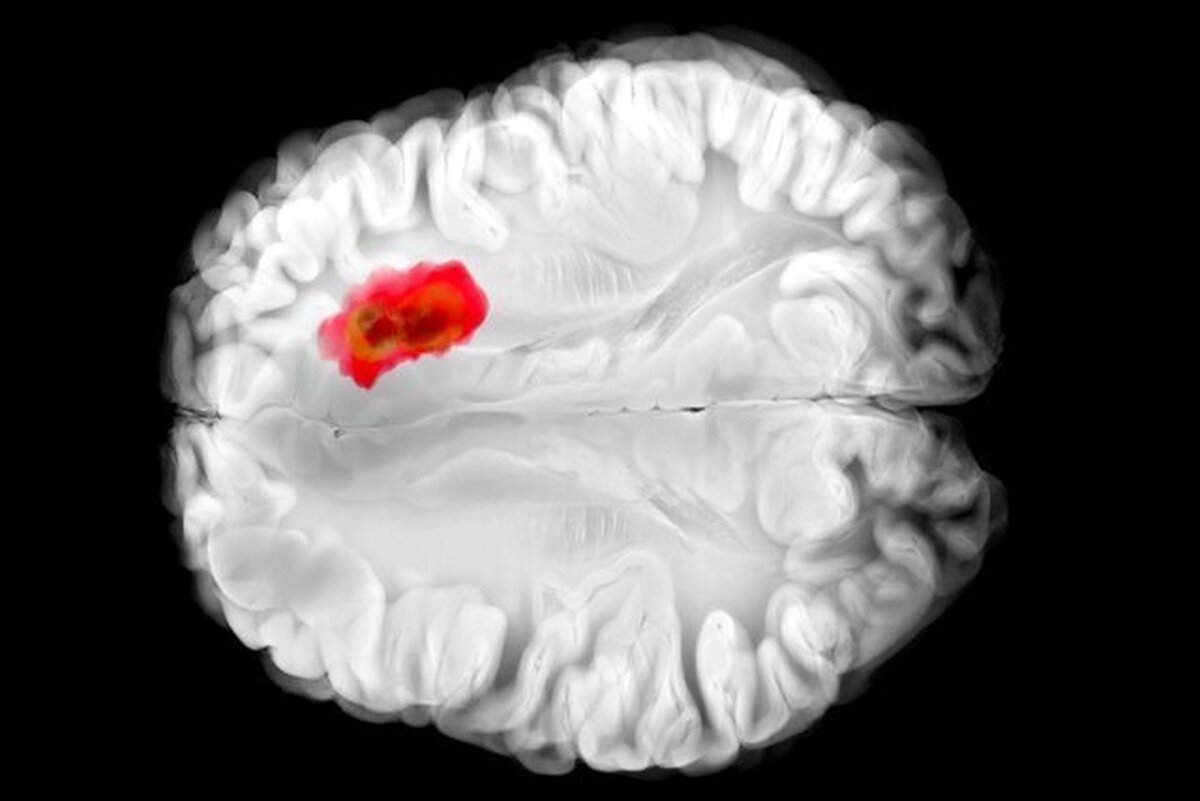

داروی کنترل فشار خون میتواند یکی از کشنده‌ترین سرطان‌های مغز را درمان کند!

به نظر می‌رسد یک دارو که پیش از این برای کنترل فشار خون بالا استفاده می‌شد، با یکی از کشنده‌ترین سرطان‌های مغز مبارزه می‌کند.

تصور می‌شود که همین آنزیم در سرطان‌های مغزی گلیوبلاستومای تهاجمی نقش دارد. این درک جدید از «هیدرالازین» می‌تواند راه را برای درمان‌های جدید سرطان هموار کند و همچنین اثربخشی دارو را برای اهداف فعلی آن بهبود بخشد.

مطالعات قبلی نشان داده‌اند که تومور‌های گلیوبلاستوما اغلب سرشار از ADO هستند و آن را برای تولید ماده شیمیایی به نام هیپوتائورین (hypotaurine) می‌ربایند که به سلول‌های سرطانی کمک می‌کند تا گسترش یابند، برای مدت طولانی‌تری زنده بمانند و فشار را تحمل کنند.

در آزمایش‌هایی که با سلول‌های گلیوبلاستومای انسانی انجام شد، «هیدرالازین» با مسدود کردن ADO رشد تومور را متوقف کرد.

البته این مطالعه هنوز در مراحل اولیه است. اثرات «هیدرالازین» هنوز باید در آزمایش‌های بالینی در افراد مبتلا به گلیوبلاستوما آزمایش شود، اما این یافته‌ها امیدوارکننده هستند و می‌توانند راهی برای کنترل شیوع این تومور‌های مغزی که به سختی درمان می‌شوند، باز کنند.